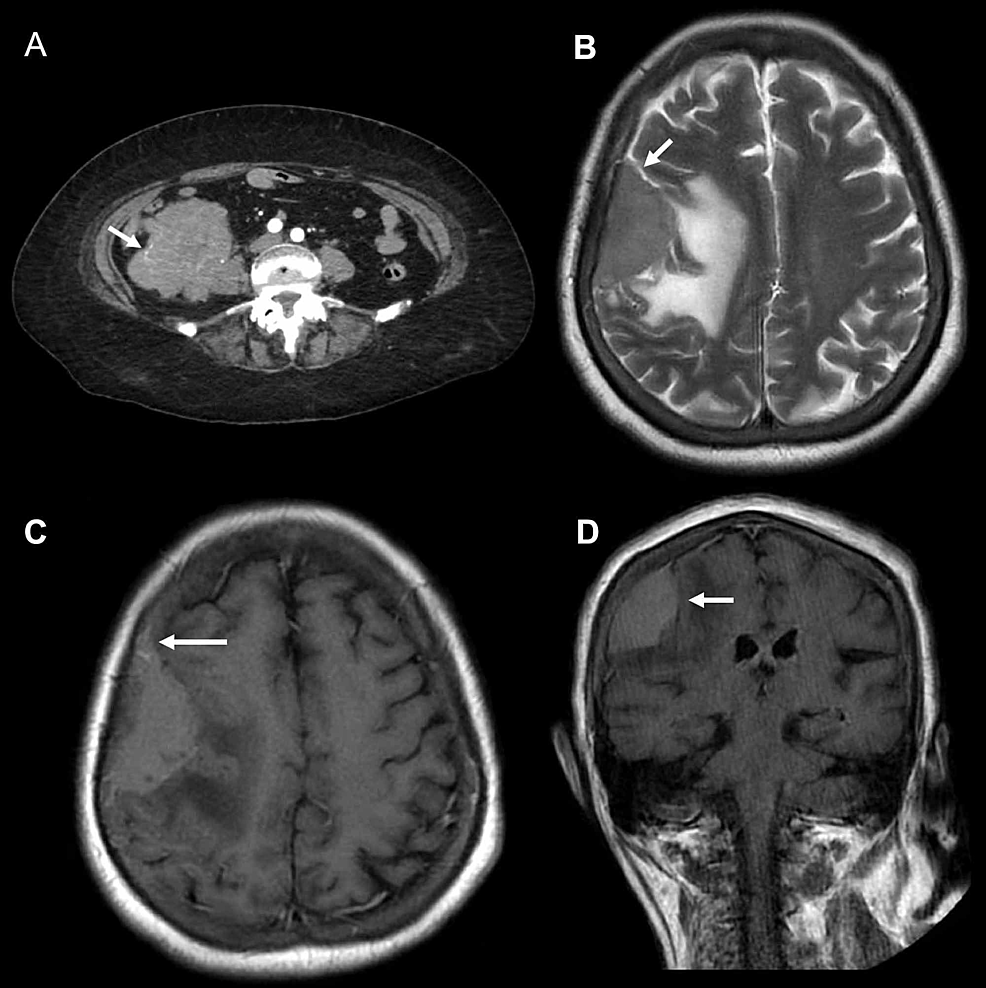

Secondary CNS lymphoma | Image | Radiopaedia.org

Secondary CNS lymphoma | Image | Radiopaedia.org from prod-images-static.radiopaedia.org

Lymphomas are tumours caused by the uncontrolled growth of the lymph cells. Because of new treatments for aids. When lymphoma has originated in other parts of the body and subsequently has spread to the cns, it is referred to as secondary cns lymphoma.

It is very important that you find the right help if you have cns lymphoma, or if. Primary central nervous system (cns) lymphoma is a disease in which malignant (cancer) cells form in the lymph tissue of the brain and/or spinal cord. Meningeal involvement occurs commonly in patients with secondary lymphoma; Lymphomas are tumours caused by the uncontrolled growth of the lymph cells.